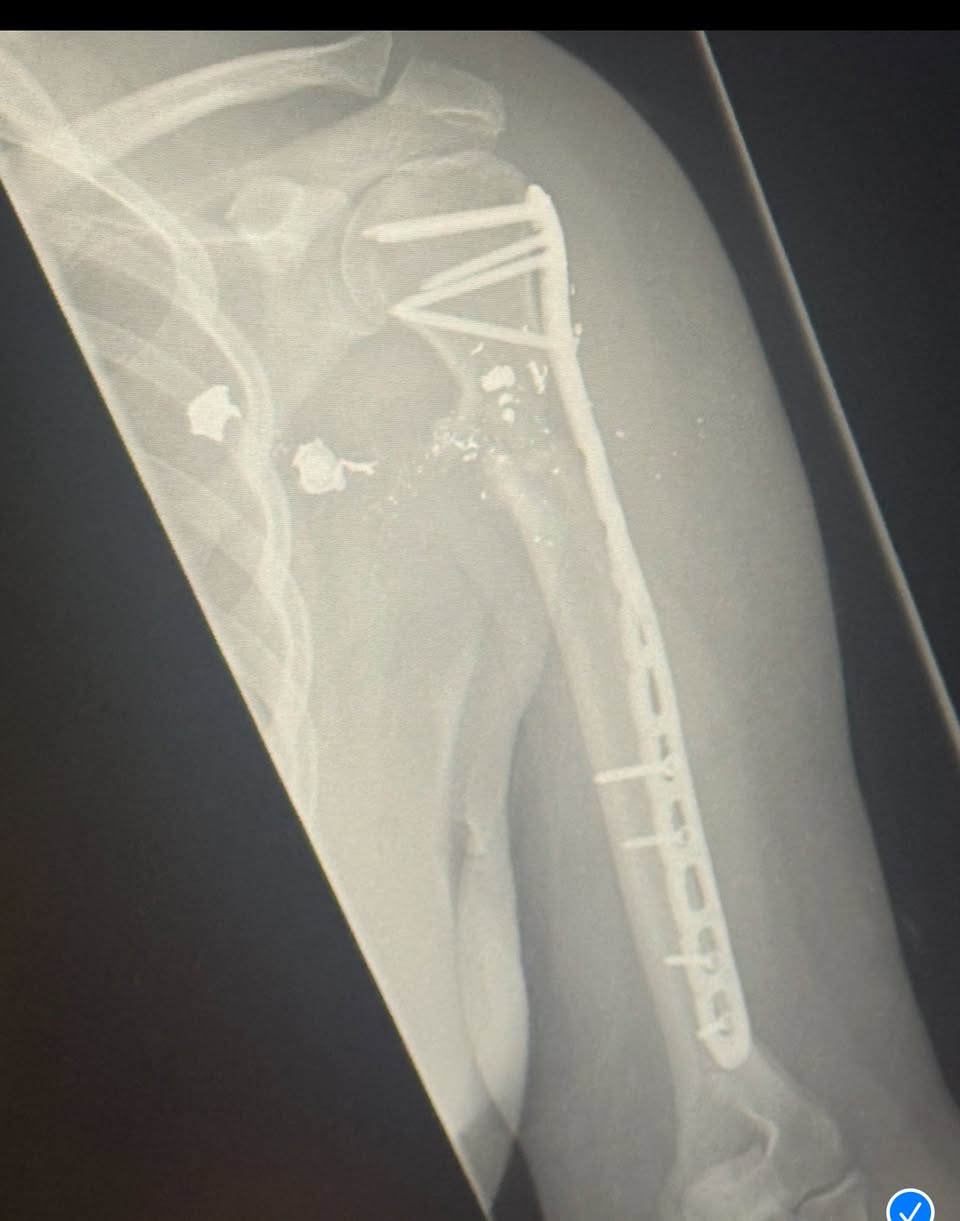

Surgeons later placed a metal rod in her arm; bullet fragments remain lodged inside, too dangerous to remove. Doctors told her it was only inches — mere inches — that kept her from dying that day.